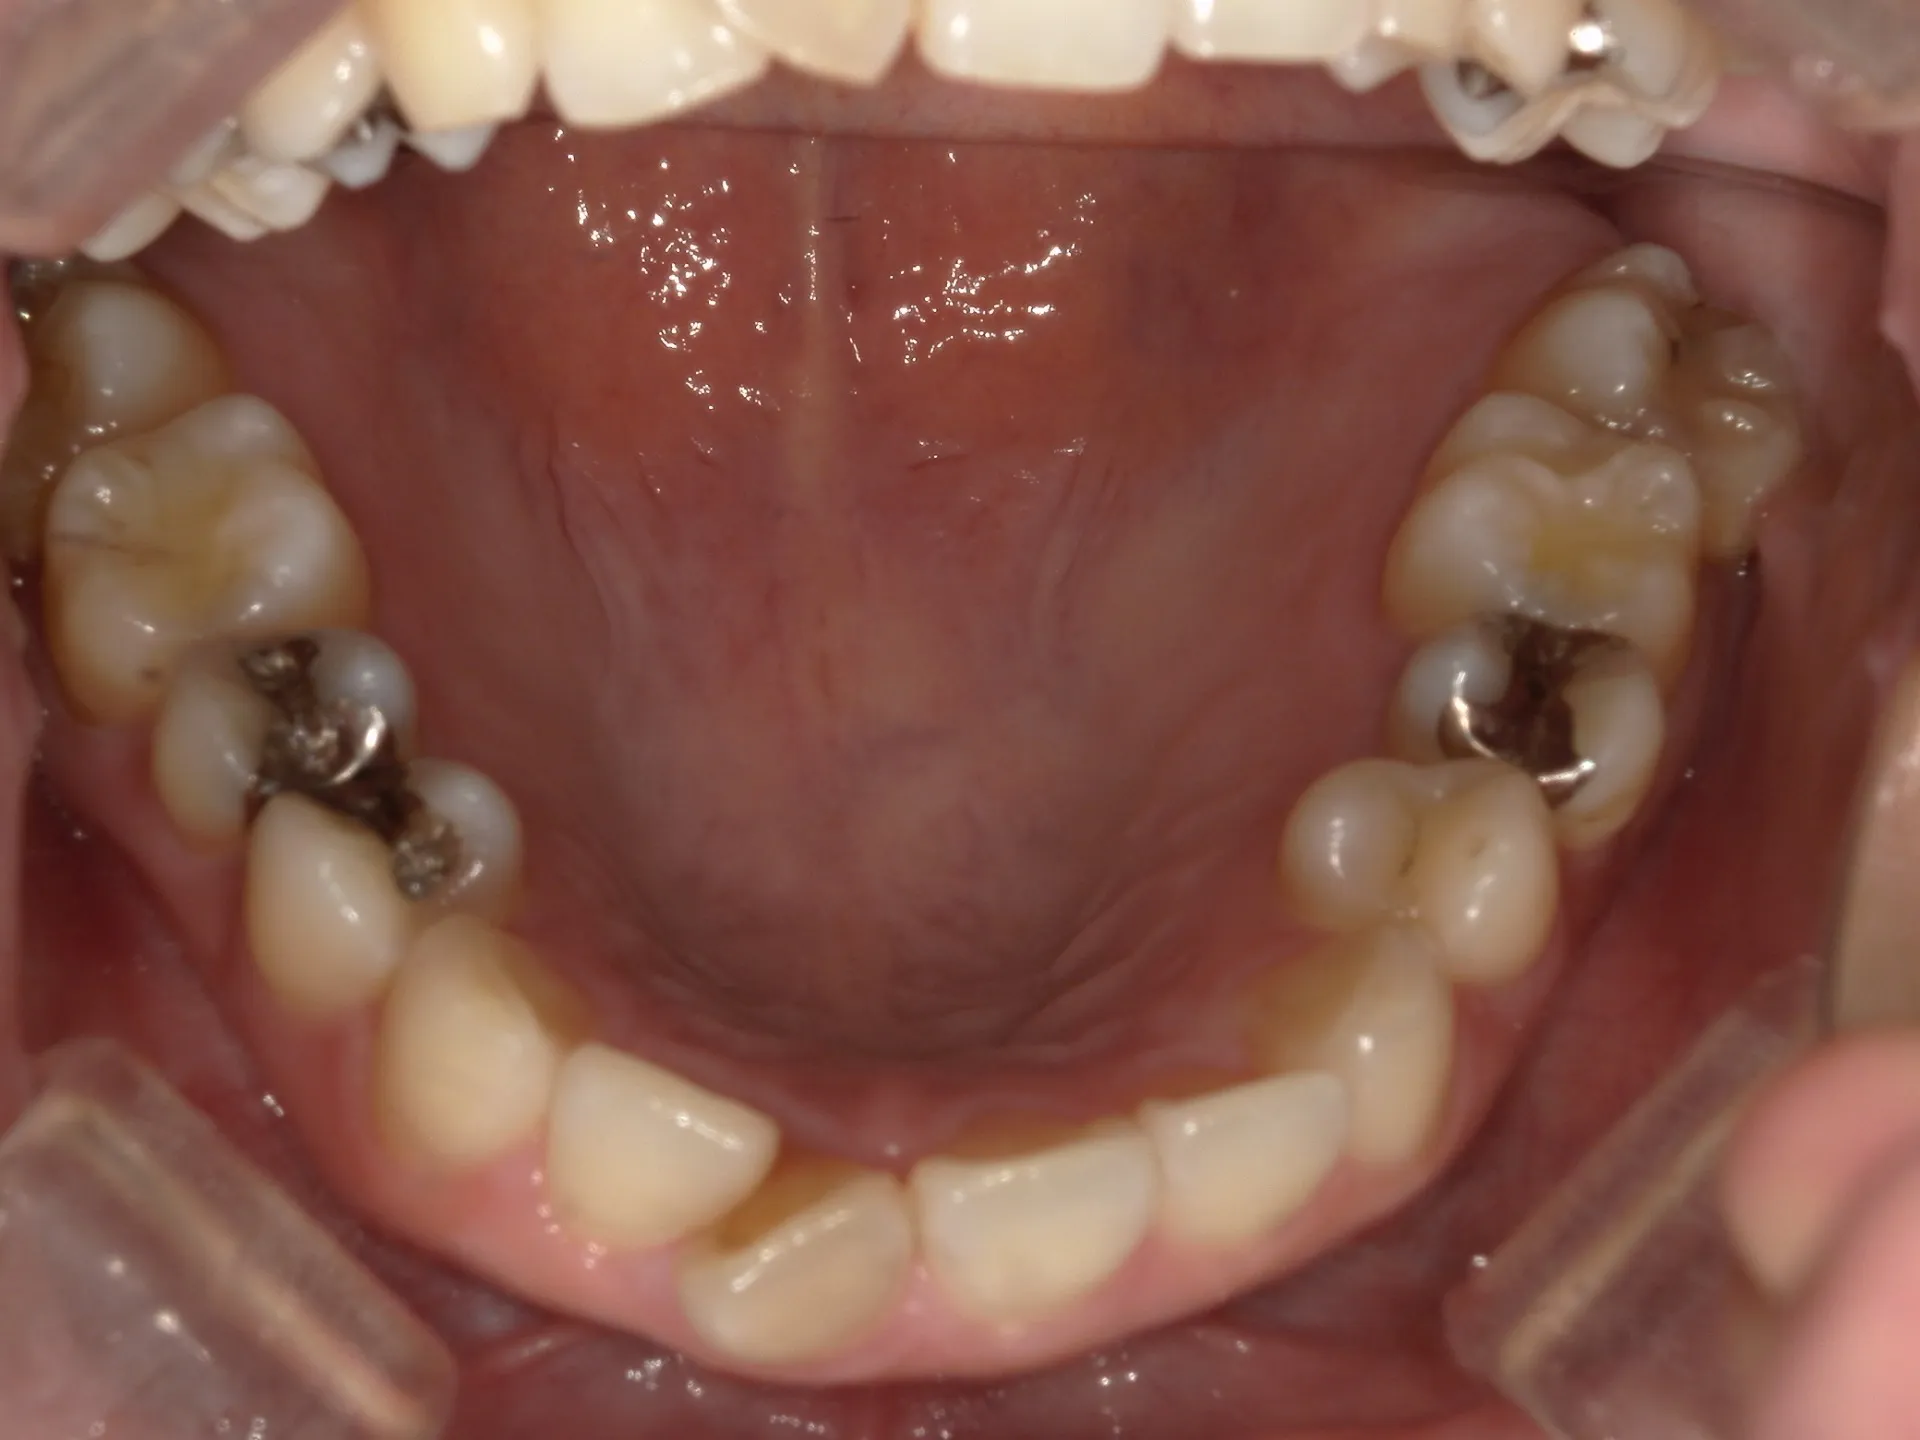

上の前歯が1本大きくねじれ、更にその歯に変色も見られました。

下の歯もスペースがなくガタついている状態の歯並びでした。

歯のねじれと歯の色を同時に治す方法として、セラミックの被せものがあります。

セラミックの被せを入れて歯の形や色、位置も治すことができますが、今回の状態で1本分のセラミックの被せを入れるとかなり細くなる被せを入れなければなりません。なぜかと言うと歯がねじれている原因は歯が真っ直ぐ生えるスペースがなかったことです。ここに無理やり被せで治そうとすると通常の歯の約半分程度の幅の被せになってしまいます。

そのため今回は通常の矯正治療とその後にご自身の歯を利用してウォーキングブリーチを行いました。

セラミックの被せ一本で治せた方が、費用感や治療期間は少なくできますが、仕上がりを考えるとやはり今回のようなケースでは、矯正治療とホワイトニングを併用した方が良い選択であったと考えられます。